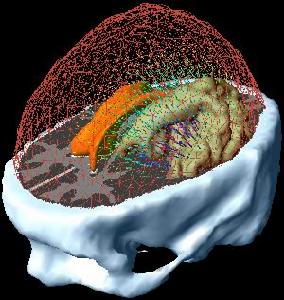

最佳治療方案

目前質子放療廣泛套用在室管膜瘤的臨床治療。質子放療與普通的X光的光子放療不同,質子放療主要有二大特點。一是可以有效的避免X光射線對腦部主要功能區的照射,並且在入射皮膚時幾乎沒有劑量的損失。二是質子射線具有布拉格峰,它可以精準的到達體內特定位置的腫瘤,在腫瘤部位實行大劑量爆破,能夠有效的殺死癌細胞,腫瘤後方沒有劑量,對後方的組織沒有傷害。在歐美,兒童腫瘤的質子治療已經納入了保險,因為質子治療可以有效的保護有效組織,這對於生長和發育的兒童來講是不二的選擇。採用先進的質子治療。

考慮到腫瘤的位置,醫生把所有可能的輔助治療選項都評估了一遍。之後,麥迪遜來到德國慕尼黑質子治療中心,通過攜康長榮國際轉診接受術後照射。質子療法可以精準地將高劑量射線束直接集中於瘤床,同時儘量避免對周圍正常組織的照射。因此質子療法對麥迪遜來說是最理想的了。而傳統的治療方法可能對麥迪遜正在發育的腦部產生長期不良影響,包括智力欠缺,內分泌功能紊亂和第二原發癌的發生。